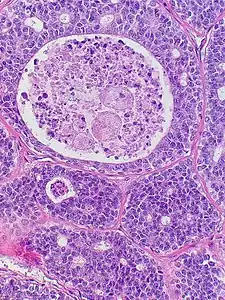

Micrograph of adenoid cystic carcinoma, fine needle aspiration specimen, Pap stain Adenoid cystic carcinoma with comedonecrosis

Adenoid cystic carcinoma with comedonecrosis Relative incidence of submandibular tumors, with adenoid cystic carcinoma being the second most common.[17]